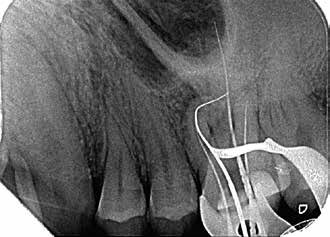

Bei der Diagnose des schmerzfreien Patienten stellte sich die beschriebene Erhebung schließlich als Fistel heraus (Abb. 1). Der Zahn 26 sowie die Nachbarzähne wurden zunächst einer Sensibilitätsprüfung unterzogen, wobei der Kältetest an Zahn 26 negativ ausfiel. Im Anschluss erfolgte dann die Anfertigung der diagnostischen Röntgenaufnahmen (Abb. 2 und 3). Dazu wurde ein Guttapercha-Stift in den Fistelgang eingebracht, um die Lokalisation der Entzündung zu erleichtern. Speziell bei der distal exzentrischen Aufnahme ließ sich dabei an 2 Wurzelspitzen des Zahns 26 die Entzündung ausmachen (Abb. 2). Insofern war in diesem Fall eine endodontische Behandlung des Zahnes angezeigt. Für diese wurde sogleich ein Folgetermin vereinbart.

Als sich der Patient immer noch schmerzfrei 4 Wochen später im Rahmen des Termins zur definitiven Versorgung in der Praxis vorstellte, war lediglich noch das Fistelmaul, aber keine Erhebung am Zahnfleisch mehr zu sehen (Abb. 4). Nachdem auch sonst keine Auffälligkeiten festzustellen waren, wurde wie geplant mit der endgültigen Versorgung des Zahnes 26 begonnen. Hierfür wurde zunächst eine Isolierung des Zahnes mit Kofferdam vorgenommen (Abb. 5). Für ein genaueres Bild vom Verlauf der Wurzelkanalanatomie lieferte eine Kontrastaufnahme mithilfe von K-Feilen und eines Silberstiftes, mb2, (Abb. 6) die notwendigen Informationen. Dabei stellte sich heraus, dass insbesondere einer der Kanäle sich durch eine außerordentliche Krümmung von beinahe 90° auszeichnete (Abb. 7).